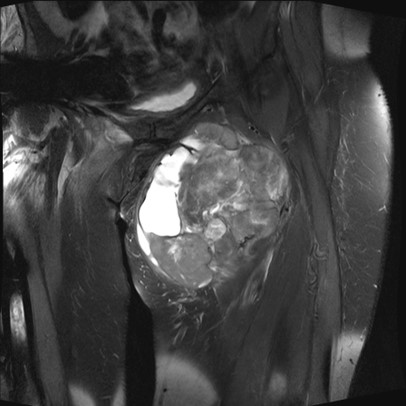

MRI